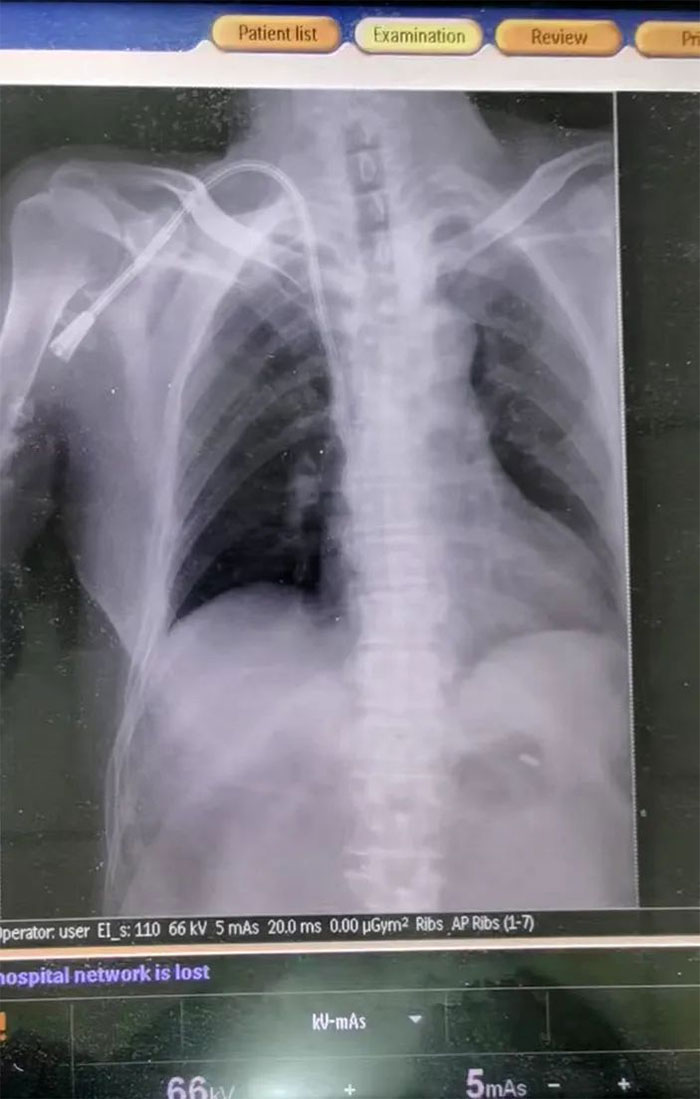

▲ DR验证,导管已经到达指定部位

情况紧急,必须尽快为患者重新构建一条长期透析血管通路。为拯救患者,经医护团队反复讨论,与患者家属充分沟通病情后,决定为患者行右锁骨下静脉长期导管置入术。在张庆成主任、李向明医生及医护团队通力协作下,最终成功为该患者建立“生命通道”,架起生命桥梁。再经过DR验证,导管已经到达指定部位,未出现出血等相关并发症及静脉阻塞症状,术后导管引血通畅,血液透析、输血顺利进行。